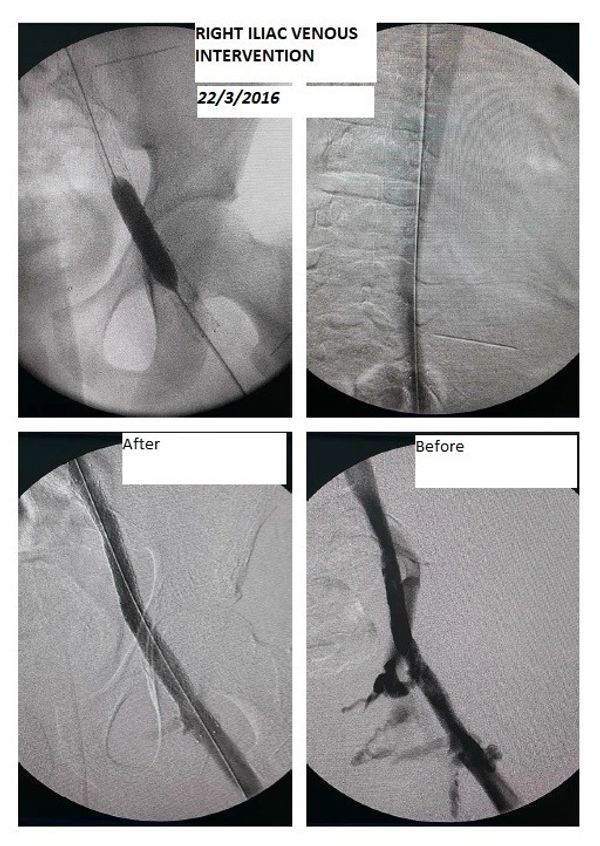

استشاري جراحة الأوعية الدموية و القسطرة التداخلية الطرفية